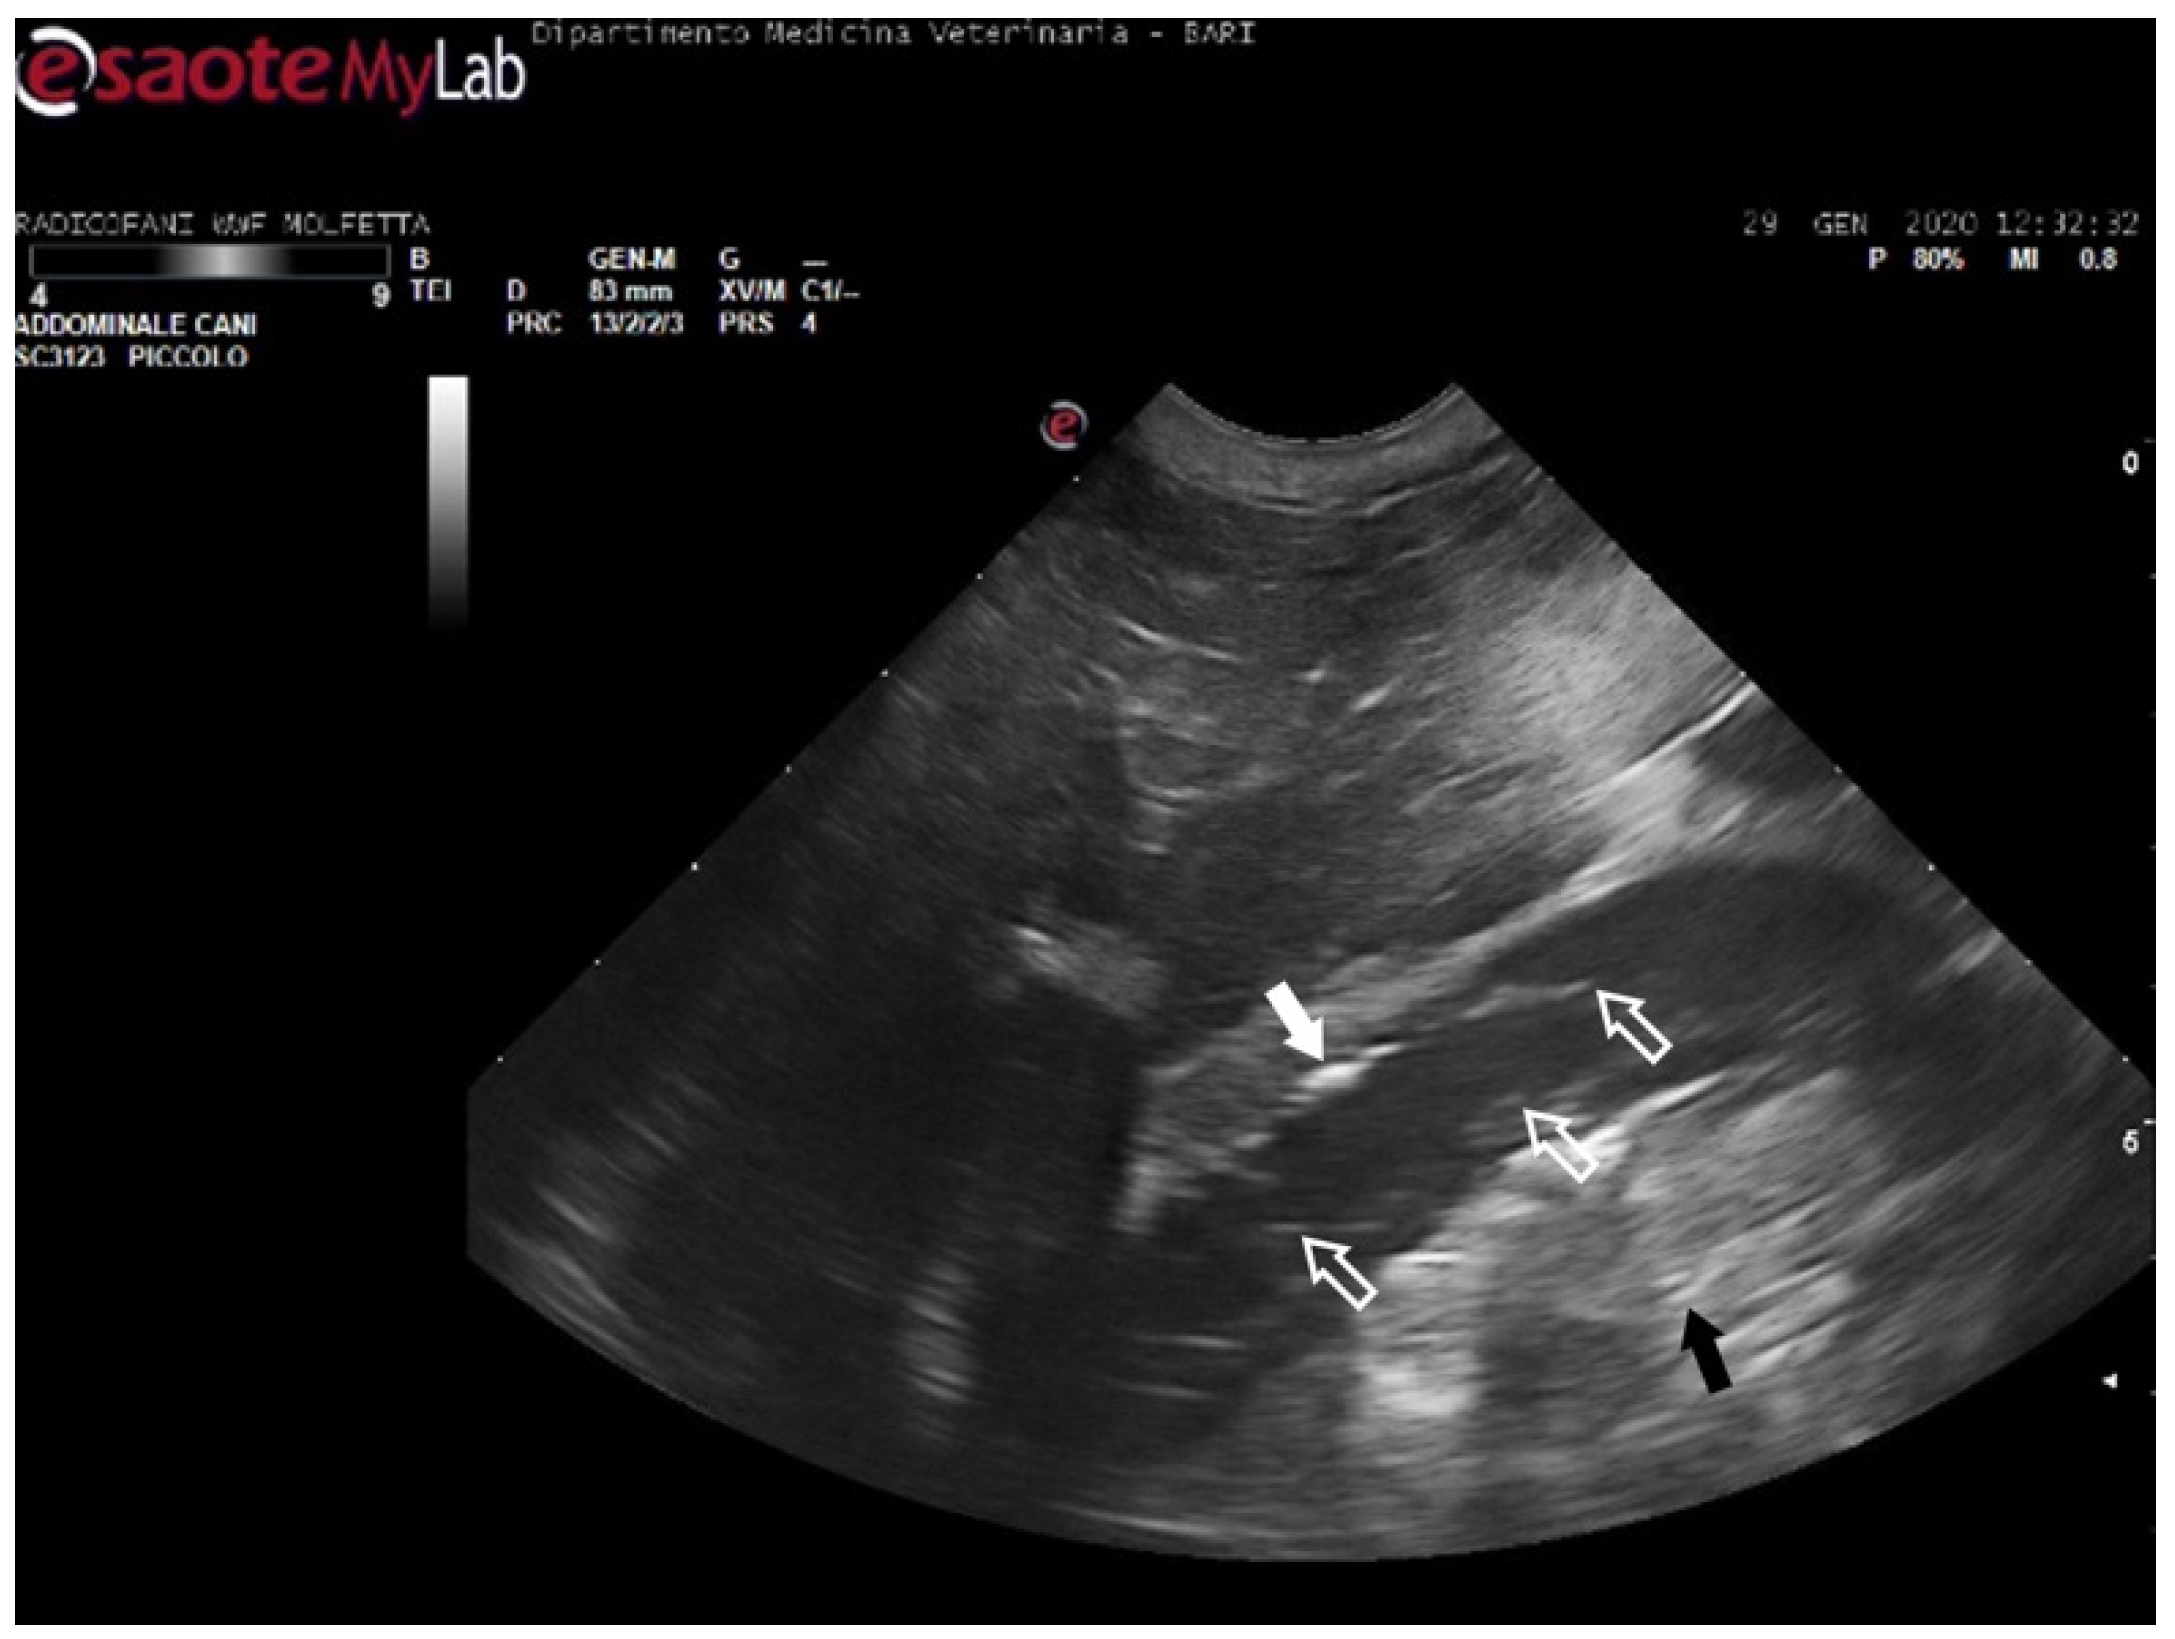

Figure 5. Ultrasound scan from the right prefemoral window shows an aggregate of medium-sized microemboli adhered to the wall of the iliac vein (white arrow), releasing very small emboli into the bloodstream (empty white arrows). The black arrow indicates the renal parenchyma.

In 11 sea turtles (37, 9%), the ultrasound examination revealed the presence of emboli in various districts, often in limited quantity. Those emboli varied in size but were generally considered microemboli. They were observed to enter the bloodstream in a cascade, resulting in slower and intermittent blood flow on Color Doppler ultrasound. Ultrasonography provided distinct visualization of the liver parenchyma and its vessels, allowing for a clear view of the intestinal loops and their associated circulation. The larger emboli were consistently found adhering to the vessel walls, while smaller emboli occasionally detached and flowed into the bloodstream (Figure 5) (Video S1).

The patients displaying these ultrasound findings were placed in the mild category following Parga’s method [17]. In some animals within this group, ultrasonography revealed emboli in multiple areas compared to those identified on radiographs. Additionally, in a turtle that appeared radiographically negative, ultrasound exams detected the presence of microemboli in the renal arteries on both sides, as well as in the left subclavian artery (Figure 6).